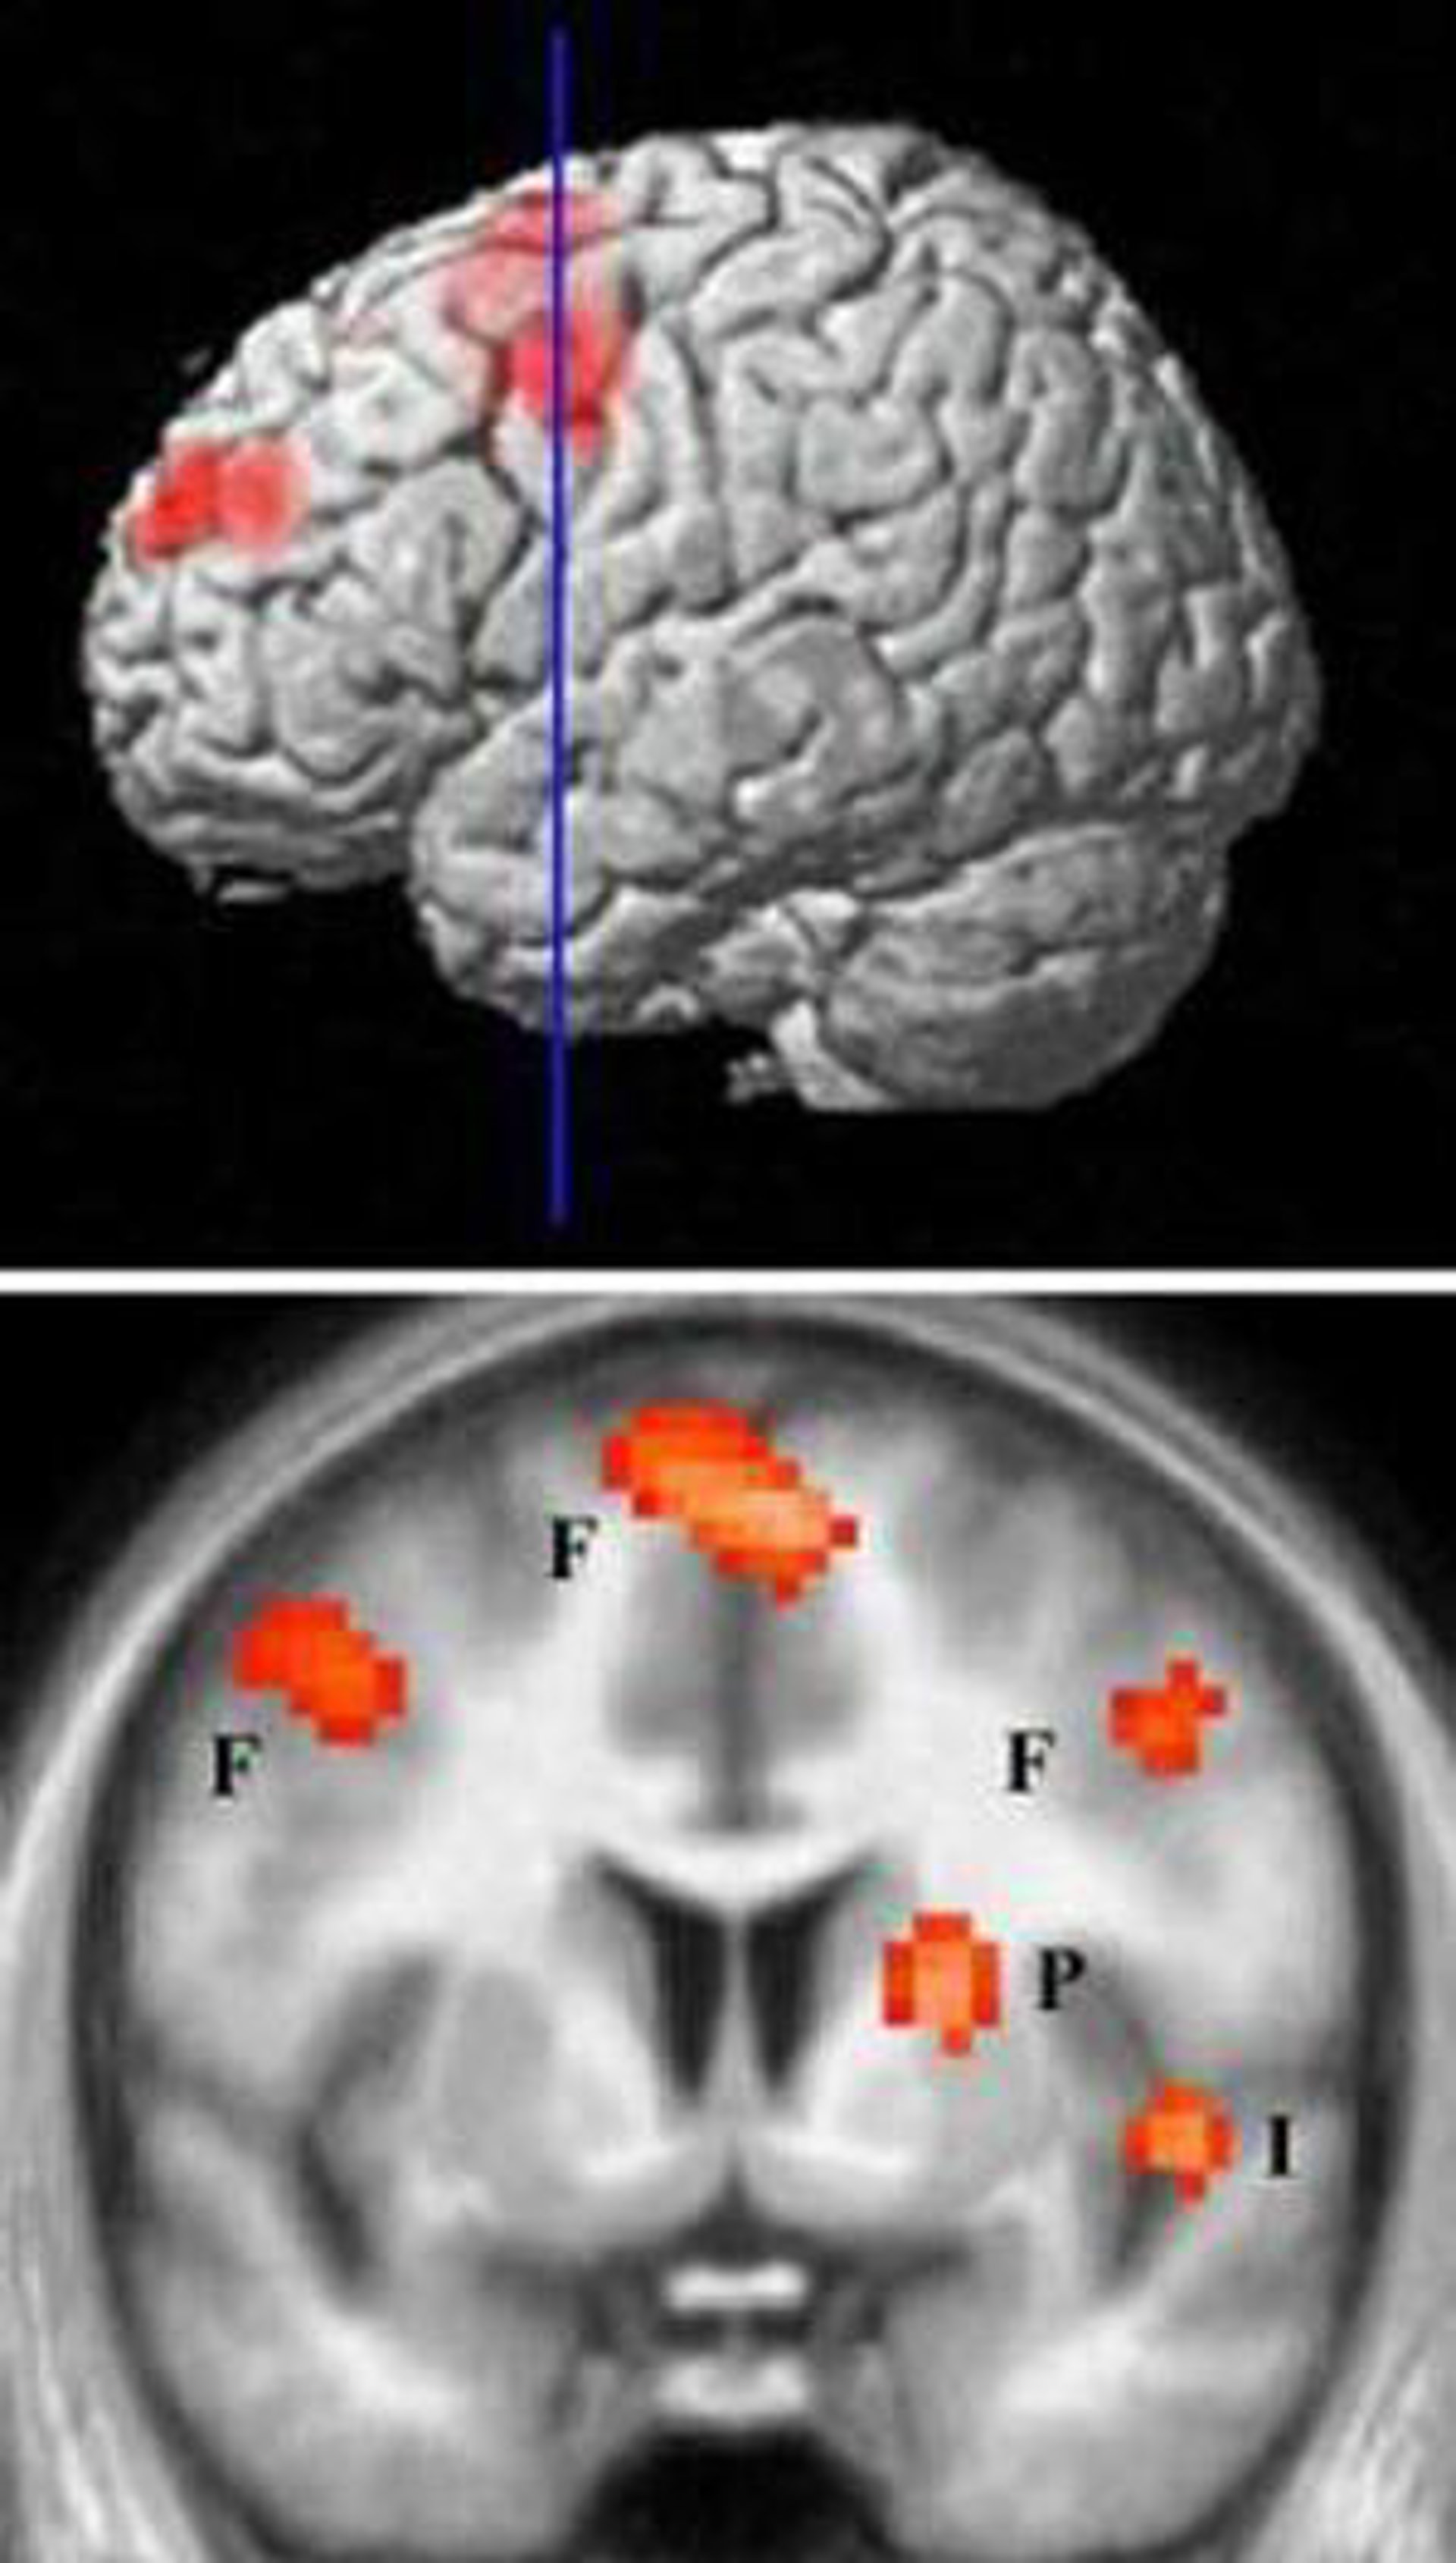

Investigadores de la Universidad de Cardiff en Reino Unido han descubierto que la actividad inhibitoria cerebral también participa en la epilepsia. El trabajo, que se publica en la revista 'Nature Medicine', apunta a nuevas dianas para el tratamiento de ciertos tipos de ataques epilépticos.

Los científicos, dirigidos por David Cope, muestran que esa actividad inhibitoria en realidad es mayor en ratones y ratas con formas de epilepsia conocidas como 'ataques de ausencia', caracterizados por una carencia de movimientos y porque los pacientes parecen "mirar al infinito".

Los investigadores descubrieron que la mayor inhibición se debe a la reducción en la recaptación de GABA, el principal neurotransmisor inhibidor del sistema nervioso. Los autores también descubrieron que esta activación selectiva de los receptores GABA era suficiente para provocar ataques de ausencia en ratones y ratas.